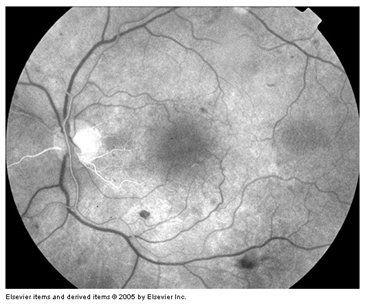

Is mainly divided into 1) blocked fluorescence and 2) vascular filling defect. Blocked fluorescence: Blocked fluorescence when stimulation or visualization fluorescein blocked by Blood. (Figure 12) (Figure 13) Pigment (Figure 14) Fibrosis vascular filling defect: (Figure 15) Vascular filling defect: Occurs when the retinal or choroidal vessels do not fill properly as in non-perfusion of artery vein. Capillary hyper fluorescence is mainly divided into 1) Autofluorescence 2) Transmission defect (window defect) 3) Leaking 4) Pooling and 5) Staining. Auto fluorescence: (Figure 16) compounds absorb blue light and emit yellow-green light in a similar fashion to fluorescein. It is imaged much more effectively by scanning laser ophthalmoscopy but can also be detected on standard fundus photography in exposed optic nerve head drusen and sometimes with Lipofuscin in retinal drusen and other abnormalities such as astrocytic hamartoma and angioid streaks. Transmission defect (window defect): (Figure 17) A window defect refers to the choroidal fluorescence produced by a relative decrease or absence of pigment in the RPE or an absence of RPE. The hyper fluorescence occurs early and reaches its greatest intensity with the peak of choroidal filling leaking: (Figure 18) Leakage of fluorescein dye is defined as hyper fluorescence of fluorescein in the extra vascular space. Typically the area of fluorescence increases in both size and intensity as the study progresses.

The borders of hyper fluorescence become increasingly blurred, & the greatest intensity of the hyper fluorescence is appreciated in the late phases of the study pooling: (Figure 19) (Figure 20) Pooling refers to the accumulation of fluorescein dye into an anatomical space. Pooling is seen in both neural retina and RPE detachments the margins of the space trapping the fluorescein are usually distinct. Staining: (Figure 21) Staining results from fluorescein entry into a solid tissue such as a scar, optic nerve tissue, or sclera the pattern of hyper fluorescence with gradually increasing intensity of fluorescence, but the borders of the hyper fluorescence remain fixed throughout the angiogram process.